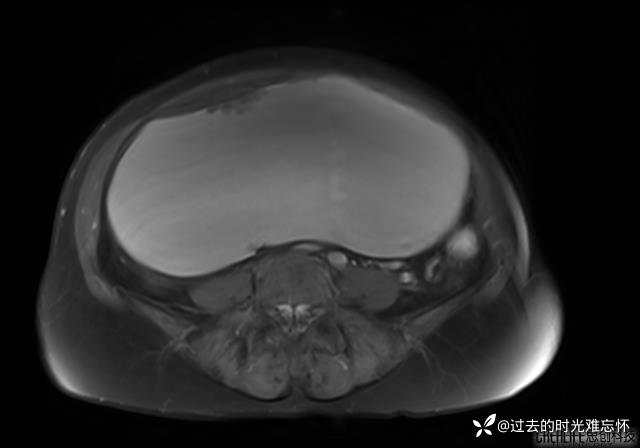

患者性别:女

患者年龄:65岁

主诉: 发现腹部隆起半年余。无其他明显不适。

浆液性囊腺瘤 (22)